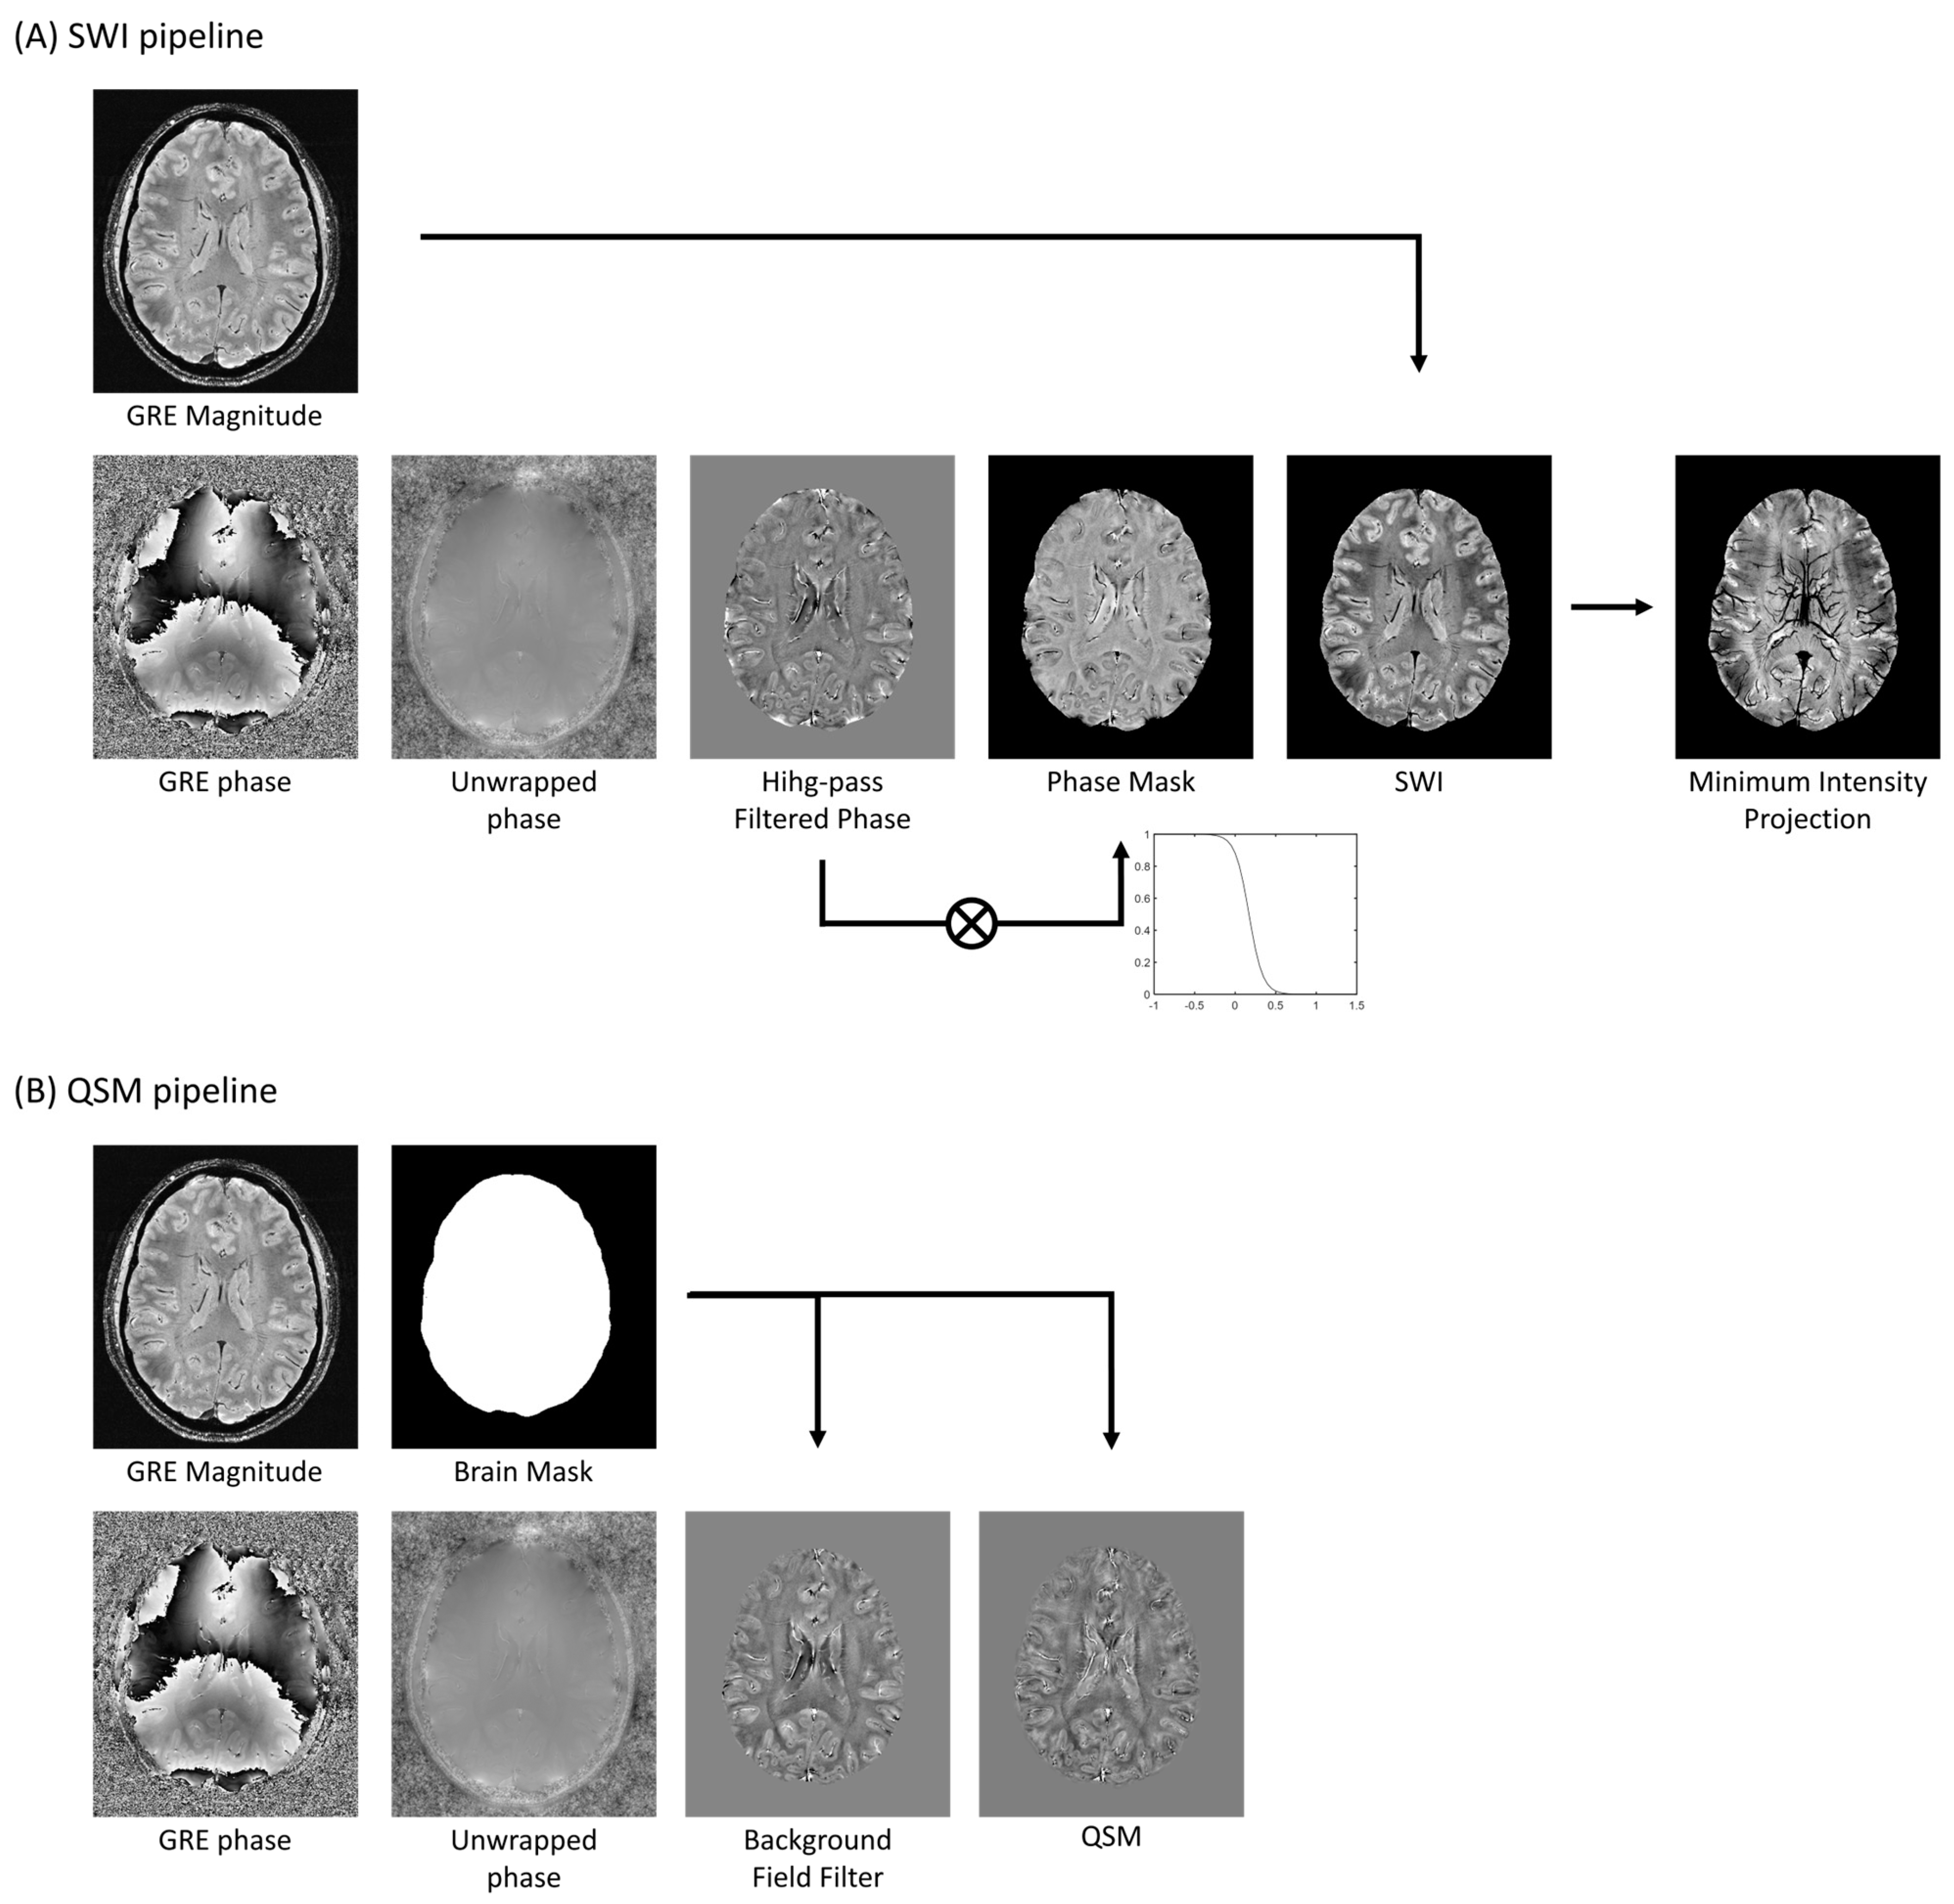

2.2. Susceptibility-Weighted Techniques